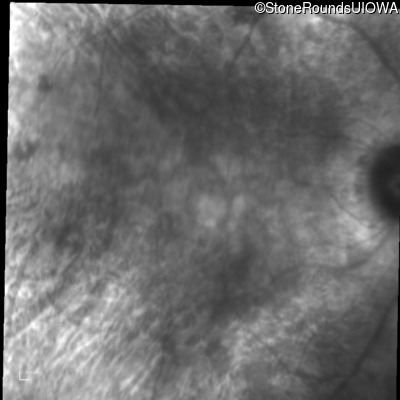

Age at visit: 53 years

OD OS

This 53 year old woman first came to attention when she had difficulty walking down stairs. A few years later she noticed difficulty seeing in dim light.

Diagnosis & molecular findings

AD Retinitis Pigmentosa PRPH2 Pro216Ser CCT>TCT   AD